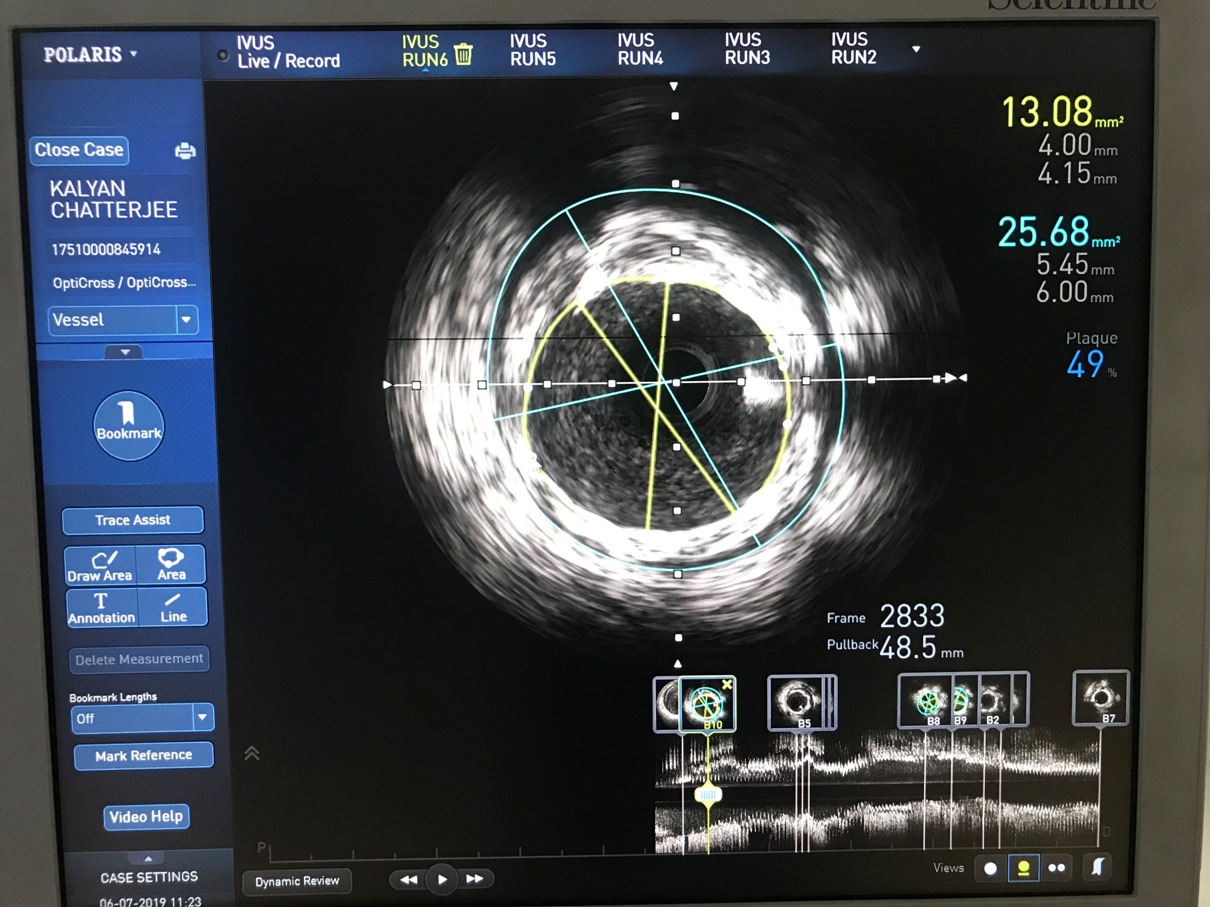

Advance Coronary Imaging